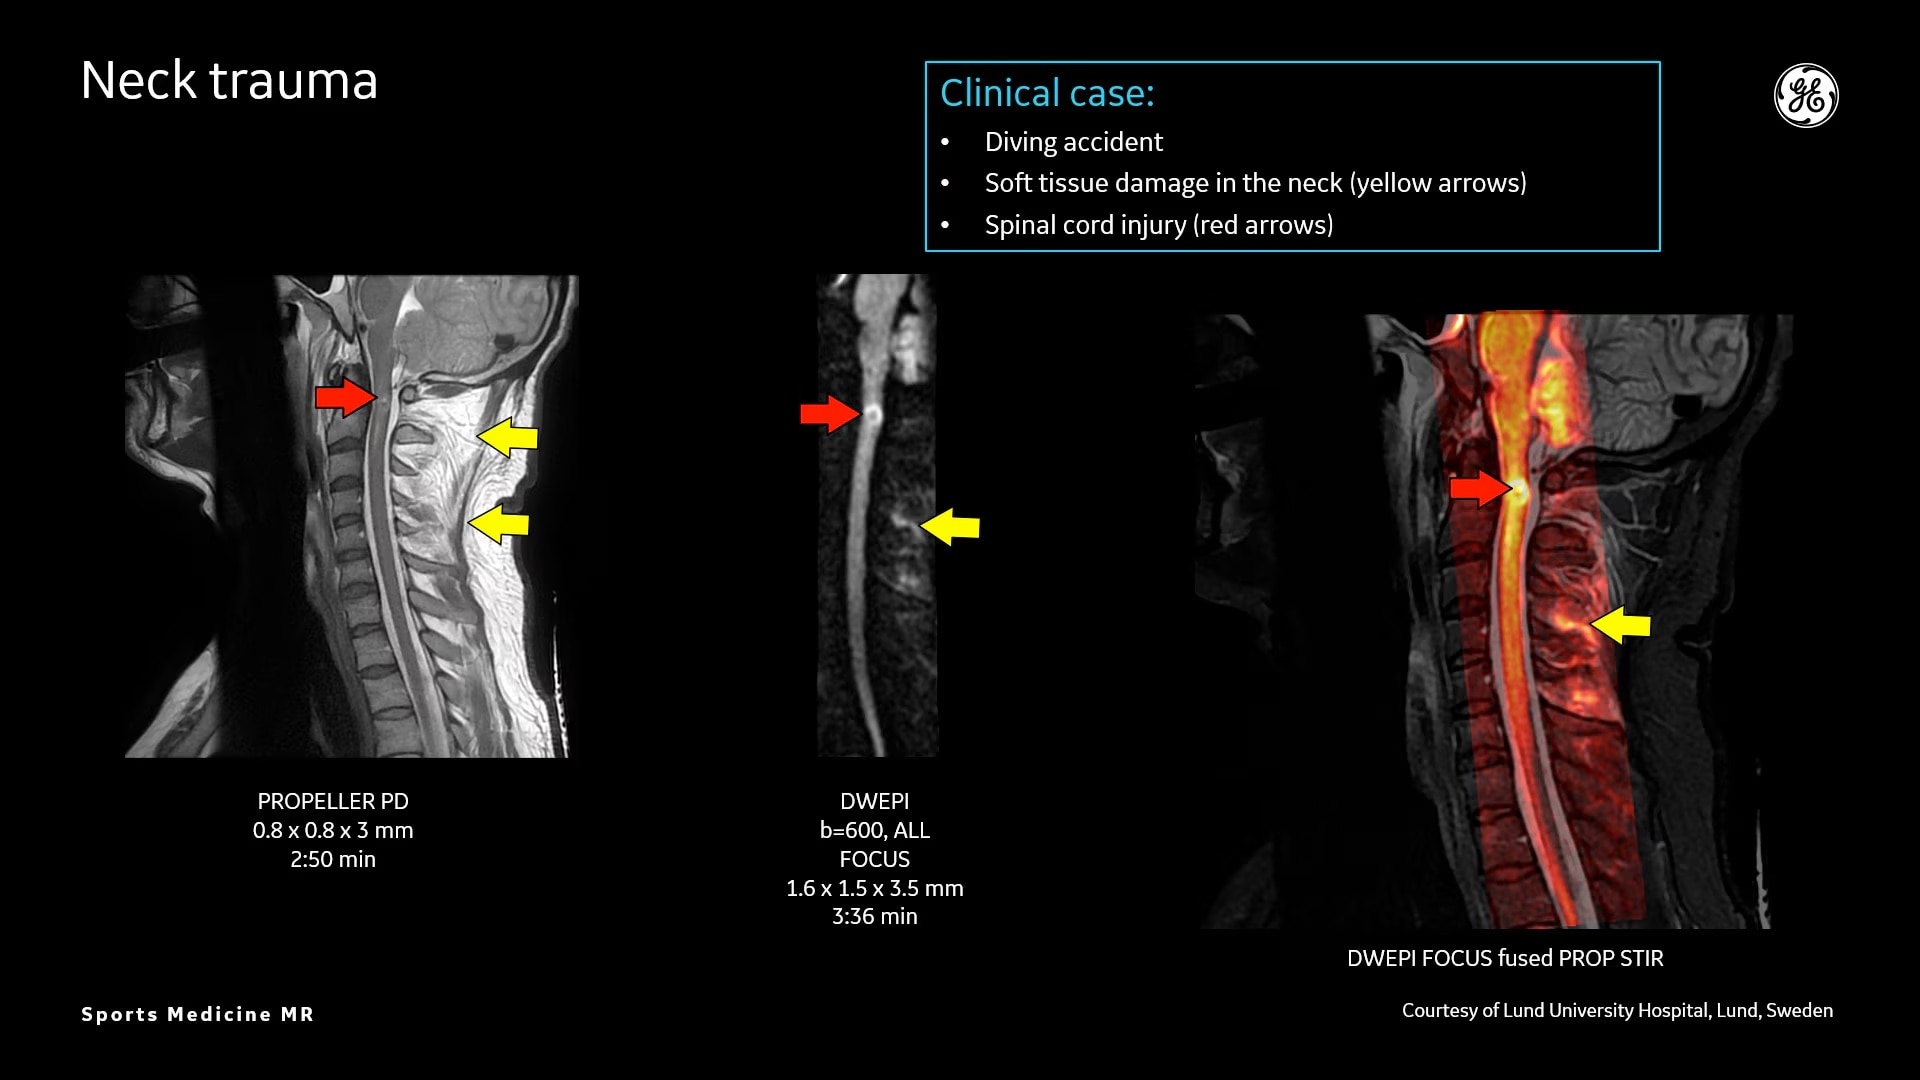

Osseous and soft-tissue injuries

MR bone imaging technology to help diagnose an athlete’s injury

MR lacks ionizing radiation, and is well-suited for longitudinal evaluation of injury in adolescent athletes. The recent introduction of the three dimensional zero-TE (oZTEo) application provides exceptional bone contrast and, like CT, can be reformatted into any arbitrary plane.